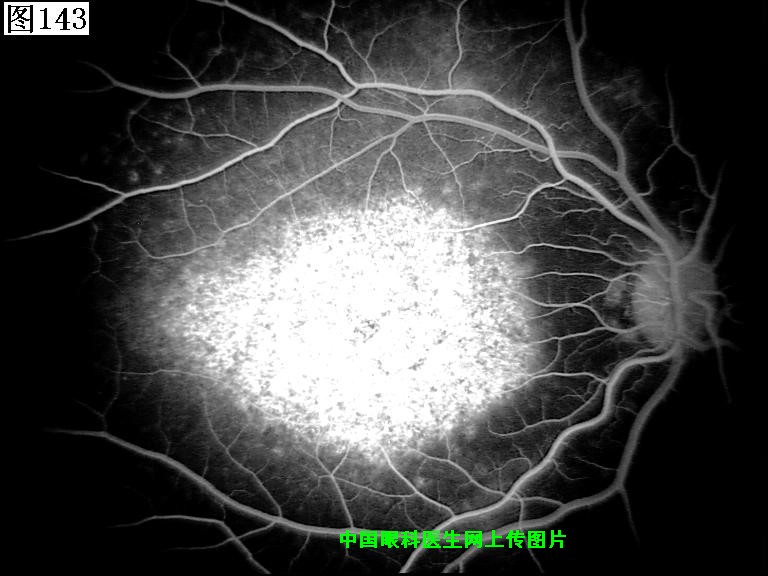

141 142 143 144